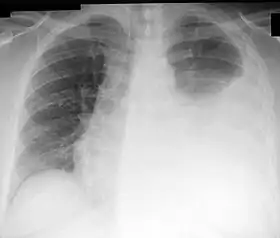

In patients who received combined treatment with Docetaxel, four of sixteen patients experienced dose-limiting toxicities at 640 mg:[4]

- Dyspnea

- Pleural effusion